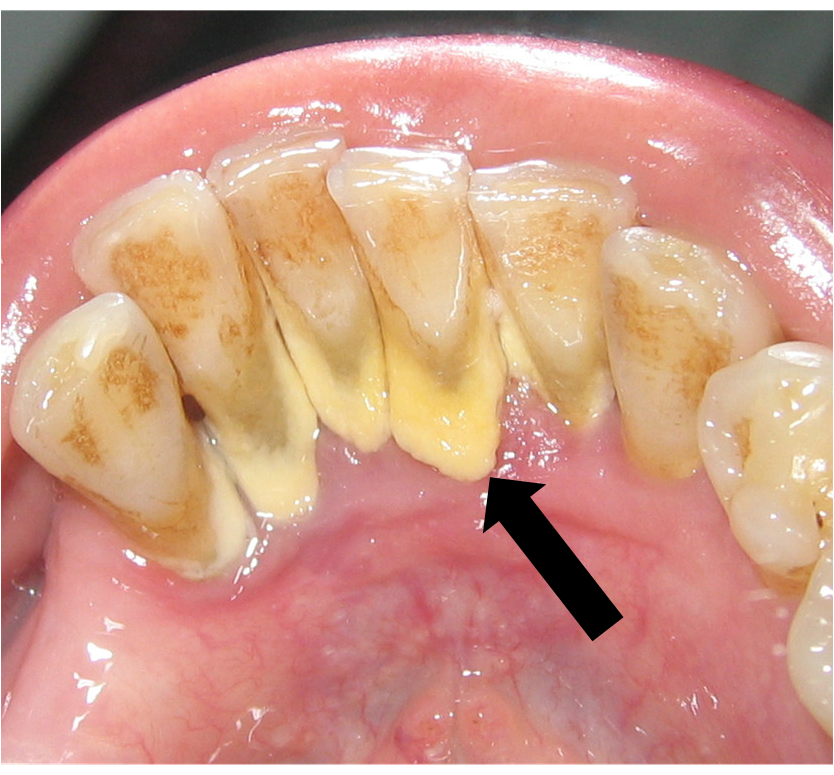

Câu hỏi: Chào bác sỹ Hoàn Mỹ. Răng của em cũng đang ngả màu ố vàng và phần cổ răng có rất nhiều cao răng. Em nghe nói vôi răng…